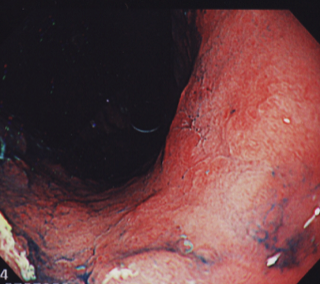

20日間ほど胃もたれが続き、市販薬でも改善しないために胃カメラ検査を受けました。

すると、胃に入ってすぐの部分から広い範囲でややくぼんだで表面が荒れた部分を発見しました。ここからガン細胞が見つかりました。

根の深さは浅そうでしたが、範囲は胃の入り口から胃の中間部分まであり、場合によっては更に広い範囲にまで広がっている可能性もありました。